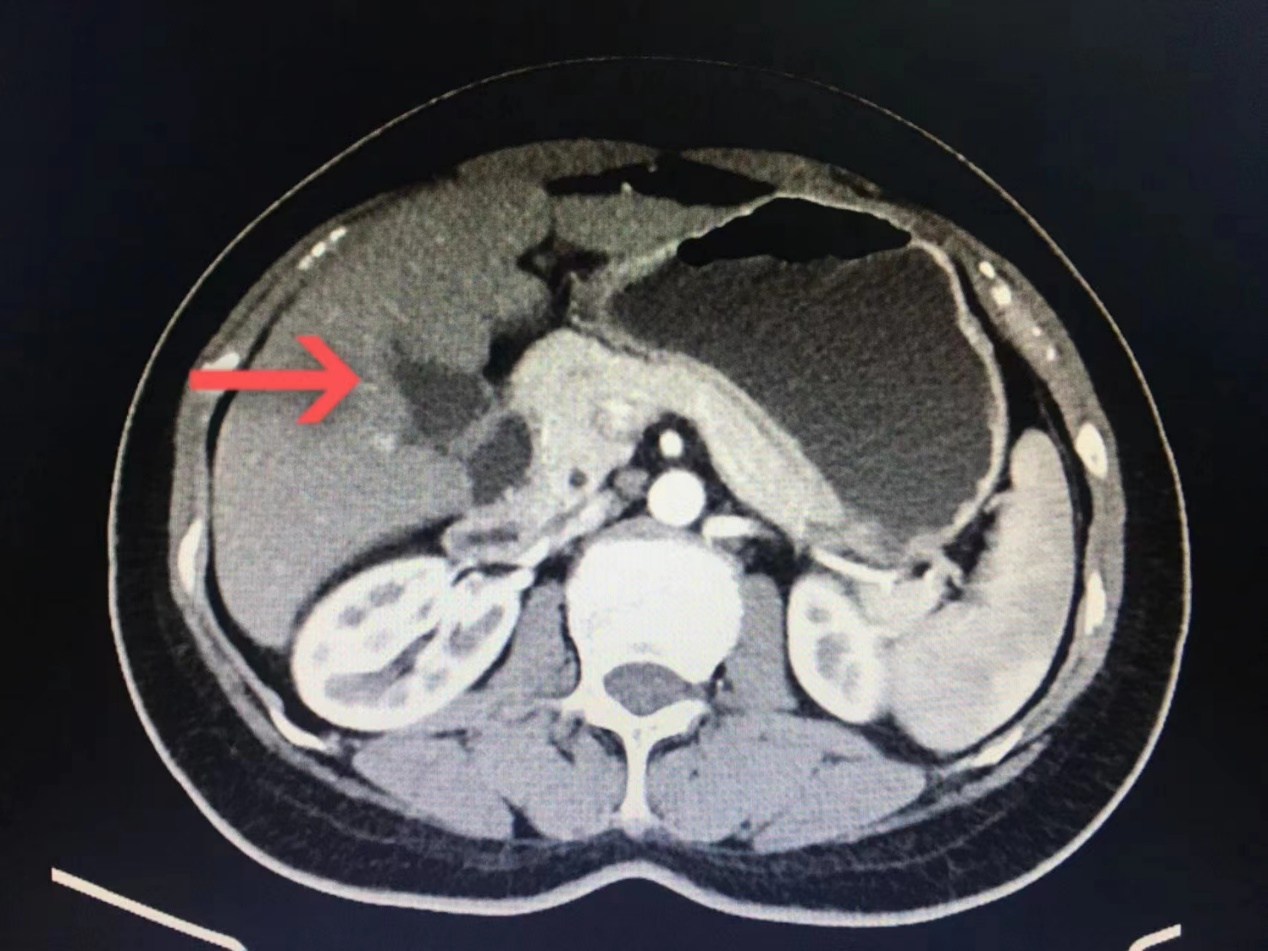

上腹部增强CT示:1.肝右叶顶部钙化灶   2.左肾静脉与腹主动脉后汇入下腔静脉   3.葫芦状胆囊   4.十二指肠淤积(请结合临床)

图1-葫芦状胆囊.png

图1  箭头标志处为葫芦状胆囊